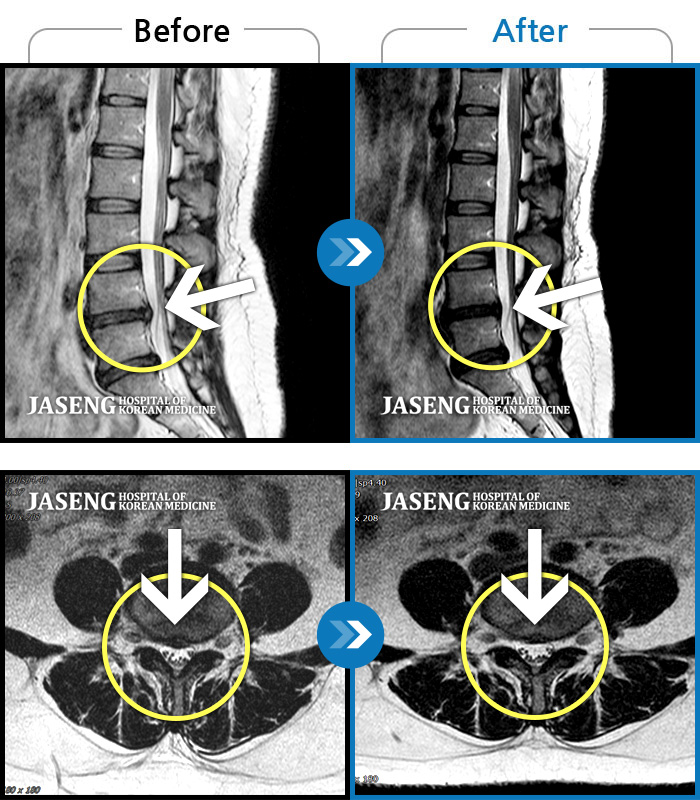

MRI 치료사례

요통으로 약침 치료를 통하여 호전이 되었다가 일을 무리한 후 요통과 하지 방사통이 심하게 발생하여 정밀 검진후 디스크 치료를 받은 환자 입니다.